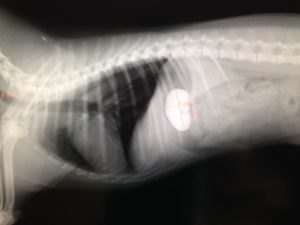

抱っこによる落下事故に注意

2016年10月10日

事故が起こったのは今年のゴールデンウィーク。

トイプードルの生後4か月の女の子が、家族旅行で訪れた蓼科高原のドッグカフェで、

飼い主さまの手から落ちてしまい、左前脚を骨折してしまいました。

近くの動物病院で応急処置を施してもらった上で、帰京後、当院に来院されました。

すぐに骨折部にプレート装着手術を行ない、なんとか歩行が可能に(写真上右)。

数か月が経過し、骨折部がしっかりと接合したのを確認し、

先日、プレートの除去手術を行ないました(写真下)。

今回の例のような旅行先はもちろん、家庭内でも、落下事故による骨折は発生します。

特に、チワワやトイプードル、ヨーキーなどの小型犬は要注意。

愛犬を抱っこする時には、くれぐれも注意を怠らないでくださいね!